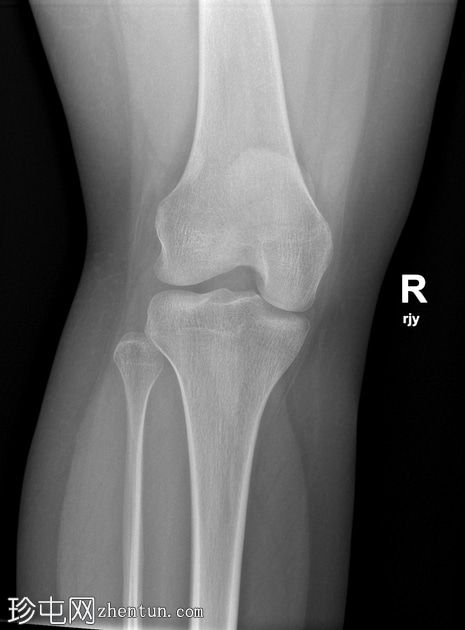

X光片

侧面

髌骨下极横向骨折。髌腱影伴有软组织肿胀,提示创伤性髌腱炎。

髌骨撕脱性骨折通常发生在下极,属于关节外骨折。这类损伤最常见于青少年和年轻人,通常由膝关节突然过度屈曲引起。从生物力学角度来看,它们与髌腱断裂类似。